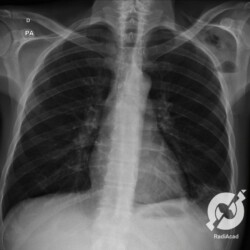

E o nome dado a esta alteração radiográfica que corresponde à substituição do ar alveolar por líquido é a consolidação alveolar.

Uma consolidação alveolar é, por definição, uma opacidade (imagem densa, branquinha) homogênea ou às vezes heterogênea (pela presença de calcificações ou cavidades), de limites mal definidos, exceto quando toca a pleura da parede ou das cissuras pulmonares. É um termo usado tanto em radiografia, como em tomografia computadorizada. Na tomografia, um outro termo é usado: vidro fosco, que é uma opacidade (branquinha mas não tanto como a consolidação), que borra o pulmão mas deixa ver os vasos de permeio (igual bigode de adolescente: dá pra ver todo o fundo).

Nós vamos mostrar aqui um pequeno apanhado de pneumonias de variados agentes, em diversos segmentos e lobos pulmonares, com extensões variadas. O objetivo é identificar o padrão radiológico de consolidação alveolar e não determinar o agente infeccioso, isso vai ser assunto para mais adiante. Aliás já antecipo que é fundamental saber localizar a lesão, porque alguns destes bichos gostam de determinados segmentos, alguns tumores também têm as suas preferências, então localização é fundamental. Se localização não fosse importante, um apartamento na beira do mar sairia o mesmo preço de um apartamento de frente pra BR-101, concordam?

Seguem alguns dos nossos casos de pneumonia para vocês treinarem os olhos e não se apavorarem nos plantões.